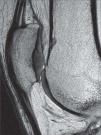

Asimismo, el artefacto por desplazamiento químico se ve reducido mediante el aumento del ancho de banda y mediante la técnica de supresión grasa, quedando bien definida el área de relación entre el cartílago y el hueso subcondral. Con todo ello, encontramos que de manera independiente, tanto el empleo de TR largos, por un lado, como la aplicación de saturación espectral de la grasa, por otro, contribuyen a mejorar el rango dinámico y la RCR. Combinadas ambas técnicas, se consigue en 3.0 T un muy alto contraste fluido-cartílago, de gran importancia para el estudio de posibles lesiones: el efecto artrográfico (figs. 8 y 9).